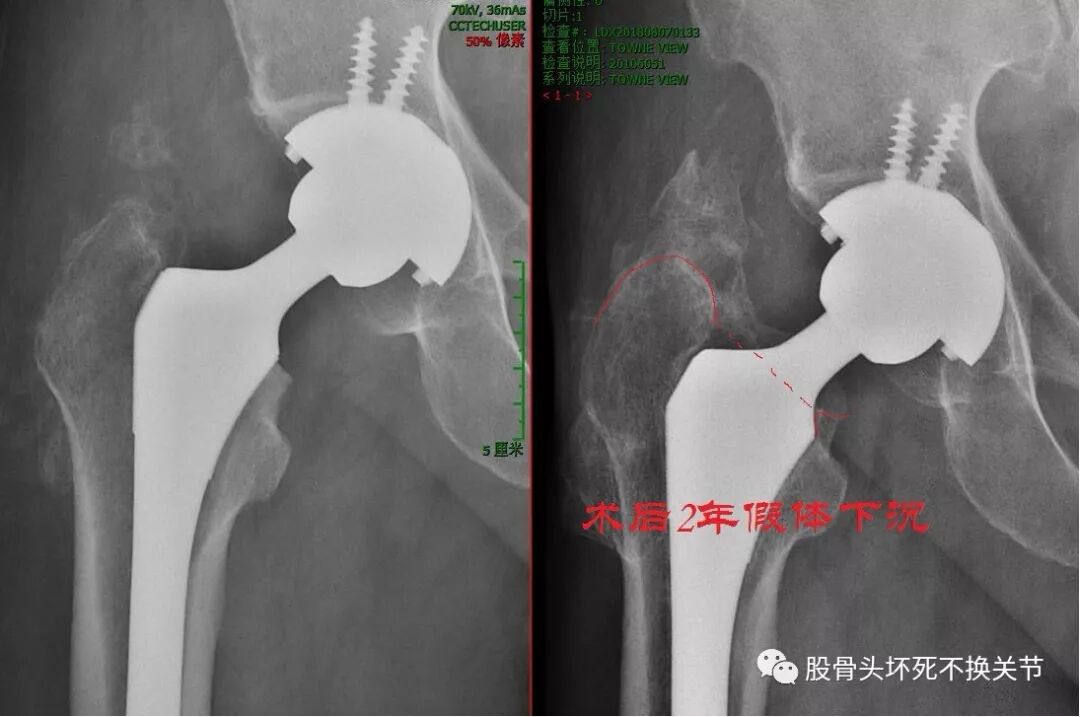

假体磨损松动病例:

男,73岁,术后10年明显磨损

年 龄:73岁   使用年限:10年   翻修原因:疼痛

假体磨损,涂层脱落

聚乙烯磨损导致骨溶解病例:

43岁,术后8年,假体磨损、骨溶解(磨损病)